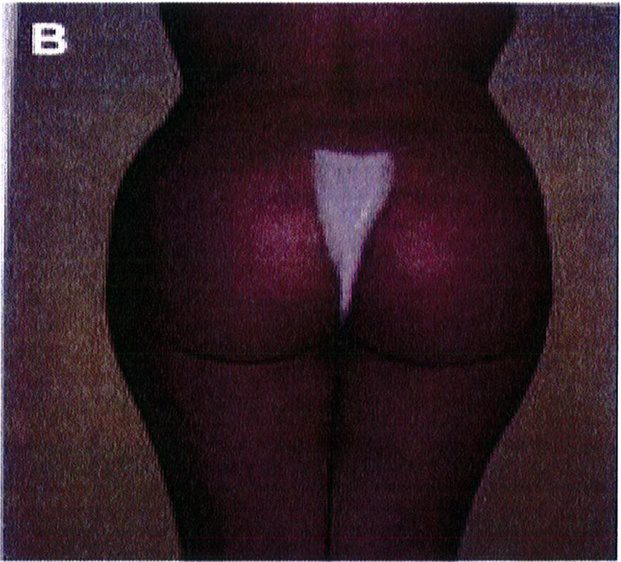

Những bệnh nhân có mào chậu rộng, khung chậu hẹp và ngắn hoặc sa hay thiếu mô mềm ở mông sẽ không phù hợp với các thủ thuật nâng mông, bất kể áp dụng ở mặt phẳng nào. Các tác giả khuyến cáo họ nên chuyển sang phương pháp ghép mỡ (Hình 2).

Hình. 2. Bệnh nhân với khung chậu quá rộng hoặc quá ngắn đều không phù hợp với implant mông.